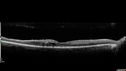

58 year old man with sudden vision loss in the right eye. The vision had been 20/40 and dropped to 20/200 the day prior to presentation. VA 20/200 OD, 20/20 OS FA shows CRAO. No cherry red spot.